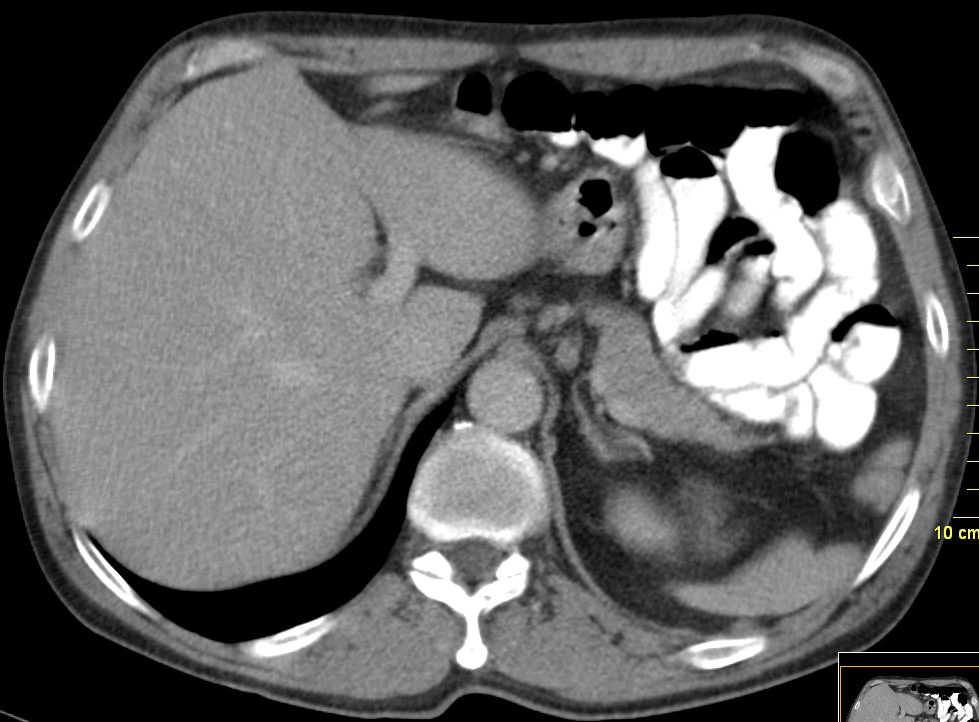

62-jähriger Mann mit schmerzhafter Schwellung des Sternums.

Die Stanzbiopsie ergab ein basaloides Plattenepithelkarzinom. Bei der Durchuntersuchung wurde ein asymptomatisches Ösophaguskarzinom gefunden.![]() |